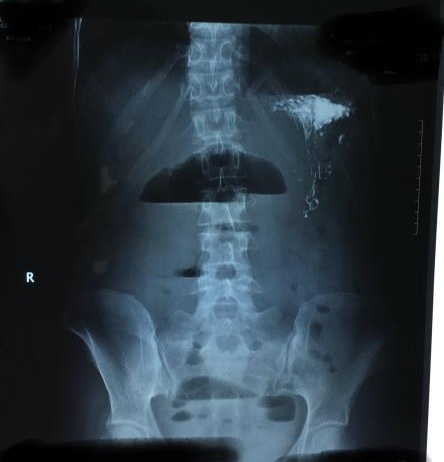

患者手术前反复发作肠梗阻的影像资料